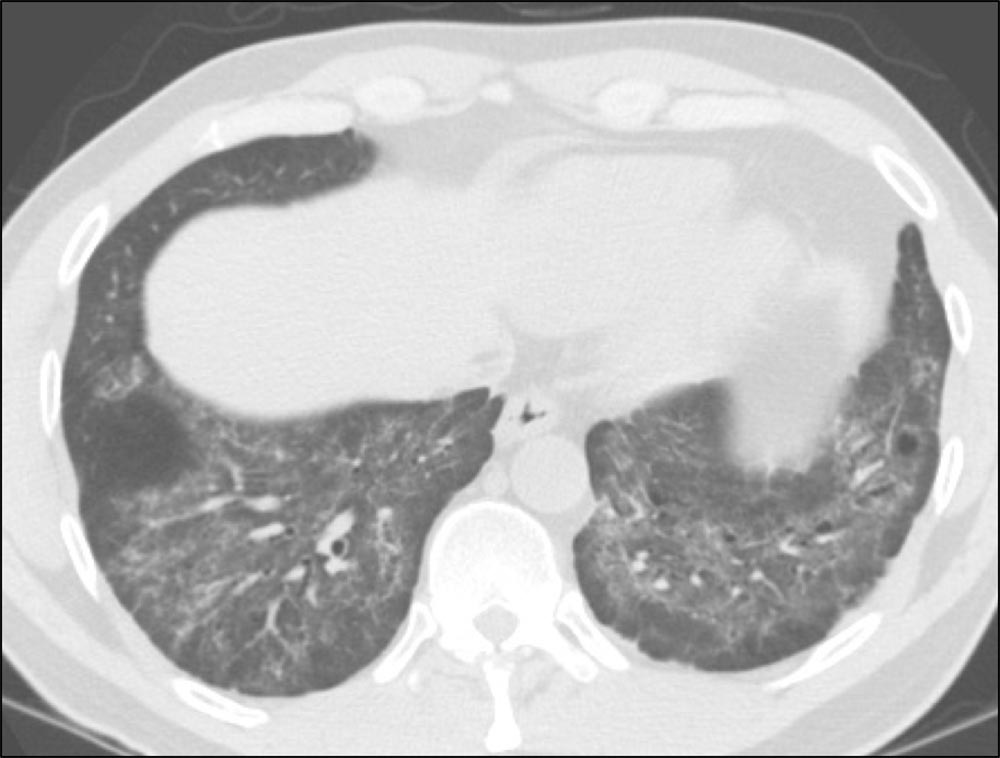

This axial HRCT scan shows a diffuse, homogeneous parenchymal abnormality with architectural distortion, traction bronchiectasis, and fibrosis suggestive of a pattern other than usual interstitial pneumonia (UIP). Note that the subpleura is relatively normal, termed subpleural sparing, a feature often seen with nonspecific interstitial pneumonia (NSIP).

Images courtesy of and used with permission from Sudhakar Pipavath, MD.